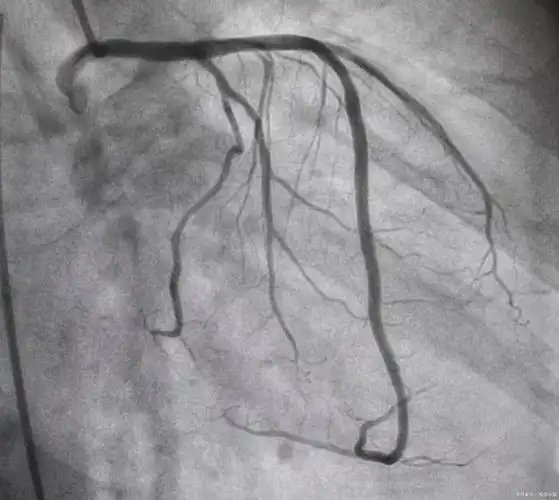

清晰的心脏冠脉造影图片!

冠脉造影——诊断冠心病的"金标准"

心脏循环有没有狭窄,下面这张图是一个有糖尿病,高血压的患者做的造影

第一例患者为中年女性,造影显示冠脉血流通畅,timi3级,继续药物治疗.